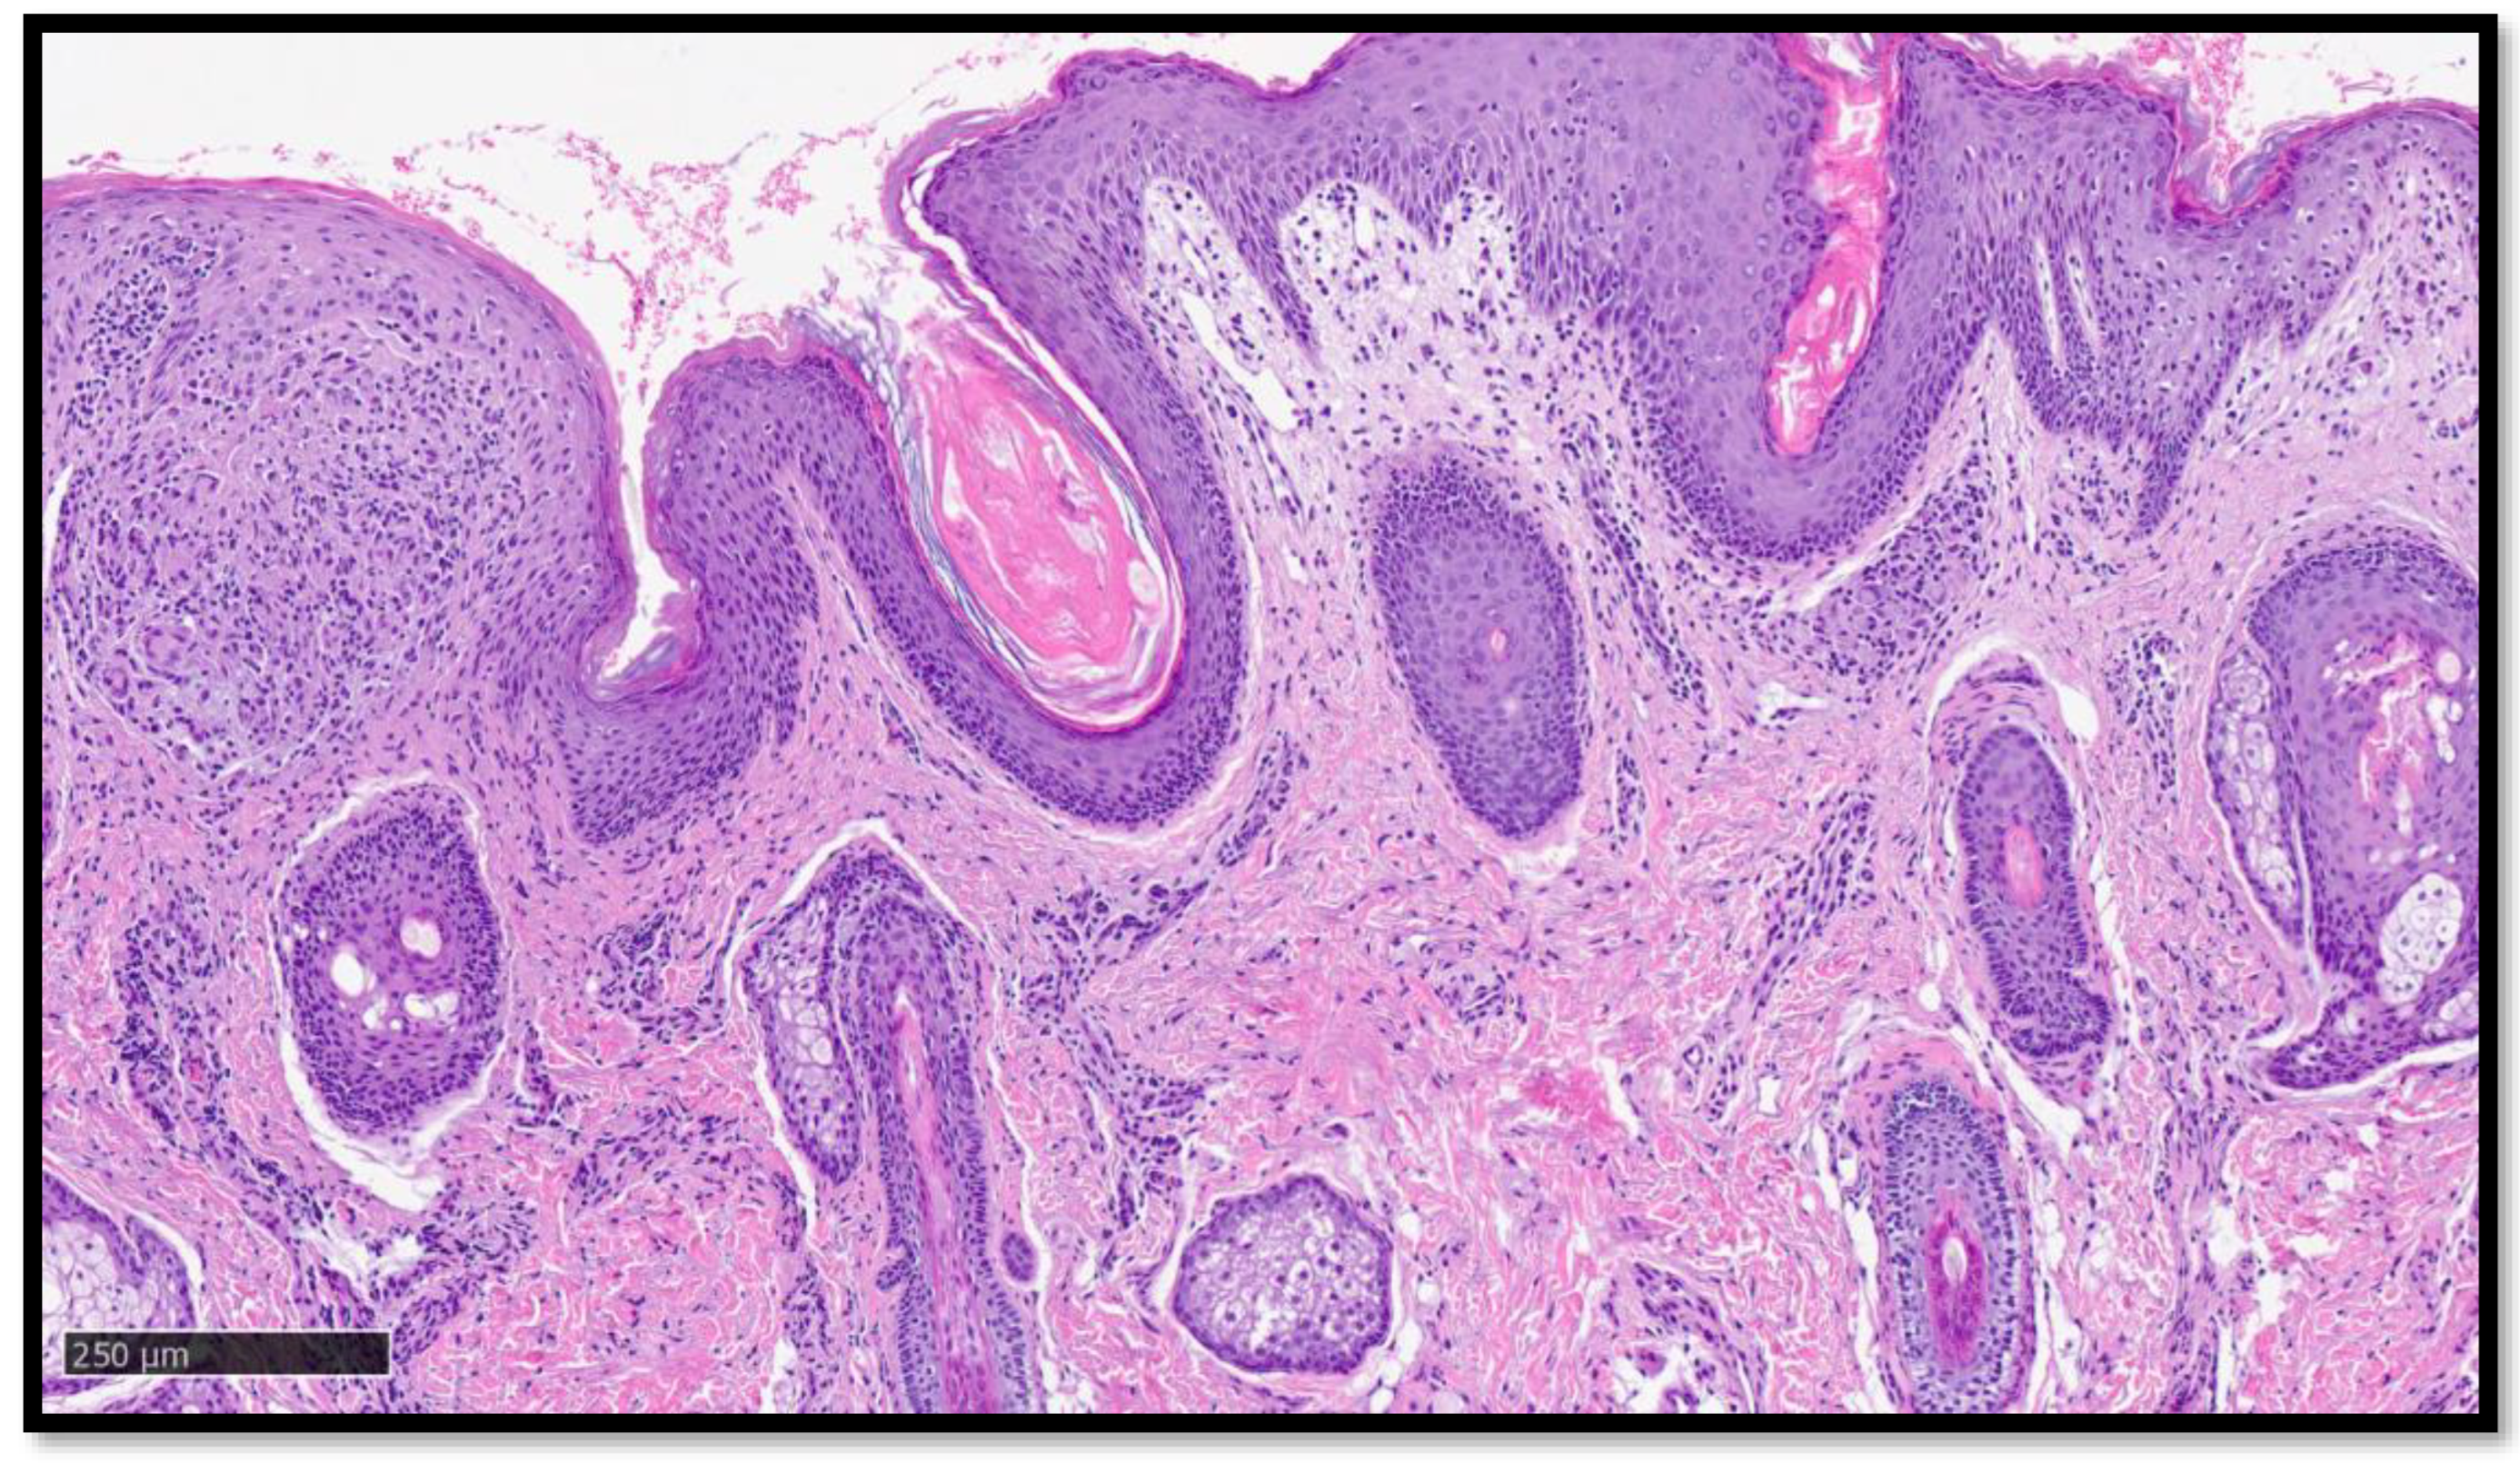

Cazzato, G.; Ambrogio, F.; Foti, C.; Capuzzolo, M.; Trilli, I.; Casatta, N.; Lupo, C.; Carrieri, M.; Daini, D.; Colagrande, A.; et al. Cutaneous Sarcoidosis-like Eruption Following Second Dose of Moderna mRNA-1273 Vaccine: Case or Relationship? Diagnostics 2023, 13, 1286. https://doi.org/10.3390/diagnostics13071286